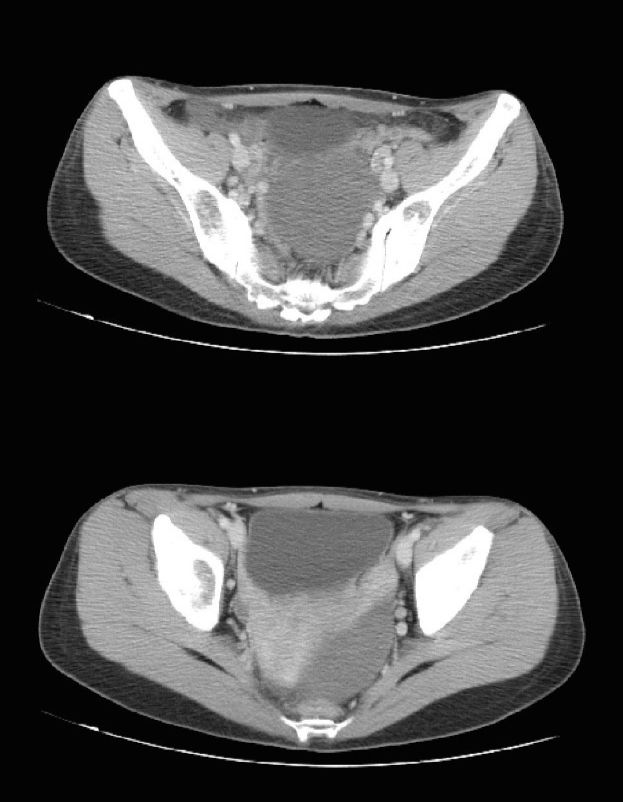

治疗前

治疗后

2周期治疗后

4周期治疗后